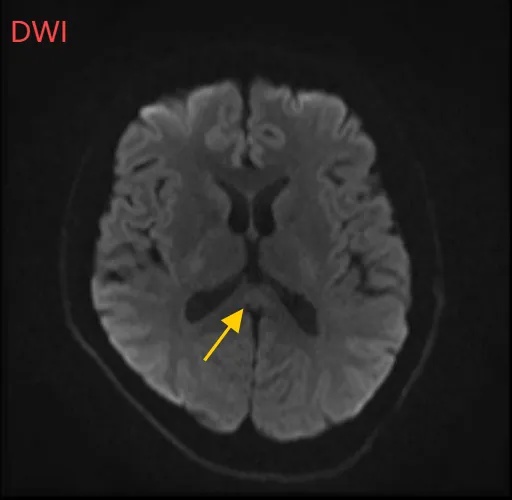

经过一周治疗,小董的胼胝体压部病变明显好转